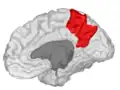

In neuroanatomy, the precuneus is the portion of the superior parietal lobule on the medial surface of each brain hemisphere. It is located in front of the cuneus (the upper portion of the occipital lobe). The precuneus is bounded in front by the marginal branch of the cingulate sulcus, at the rear by the parieto-occipital sulcus, and underneath by the subparietal sulcus. It is involved with episodic memory, visuospatial processing, reflections upon self, and aspects of consciousness.

The precuneus is located on the inside between the two cerebral hemispheres in the rear region between the somatosensory cortex and forward of the cuneus (which contains the visual cortex). It is above the posterior cingulate. Following Korbinian Brodmann it has traditionally been considered a homogeneous structure and with limited distinction between it and the neighboring posterior cingulate area. Brodmann mapped it as the medial continuation of lateral parietal area 7.